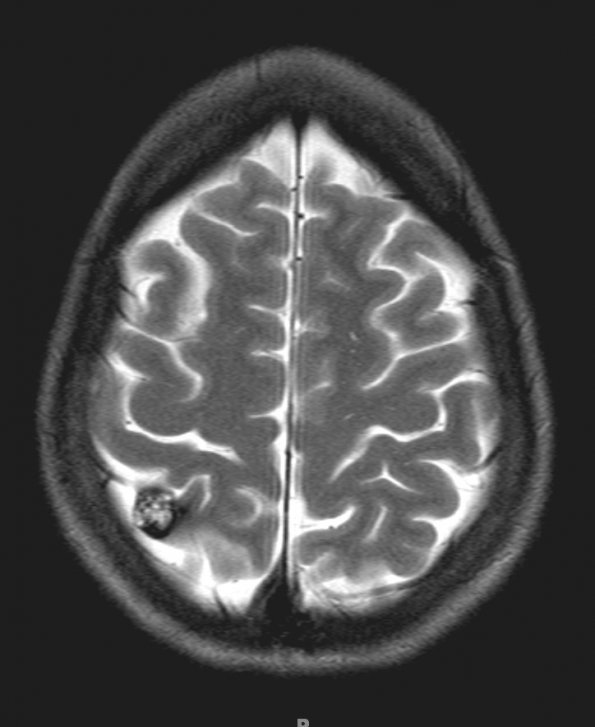

Washington University Experience | VASCULAR | Cavernous Angioma | 10A2 Cavernoma (Case 10) T2 without contrast - Copy

MRI study showed a discrete lesion with a ferruginous penumbra as seen by T2-weighted sequence without contrast.